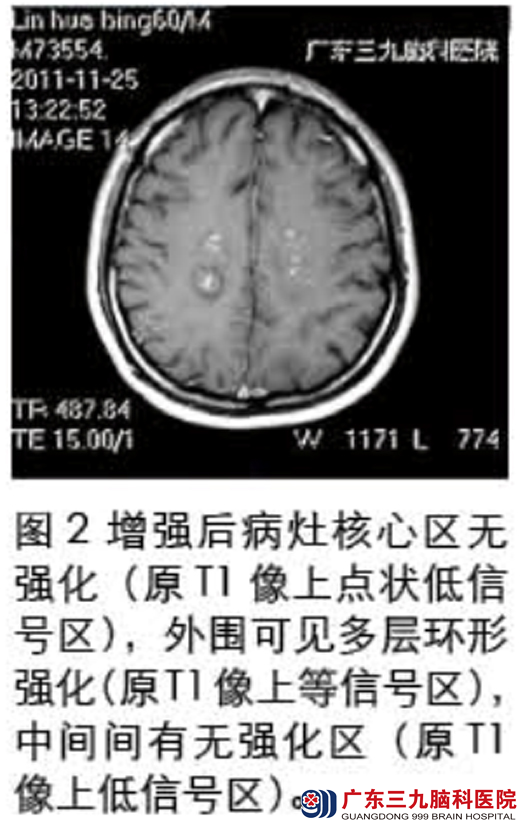

入院查体见双下肢肌力减退,肌张力偏高,腱反射亢进。头部磁共振检查示:双侧半卵圆中心多个长T1长T2病灶(见图1),伴强化(见图2),DWI序列ADC值升高(图3),MRS提示Cho峰稍有升高,NAA峰有所下降,Cr峰未见明显变化,可见Lip/Lac峰(见图4);腰穿结果:脑脊液常规正常,生化提示蛋白升高,寡克隆带阳性。确诊为Balo同心圆硬化,给予激素冲击、营养神经治疗。治疗后复查头部磁共振提示:颅内多发病灶范围较前明显缩小,异常强化程度较前减轻(见图5)。入院治疗一个月后林先生好转出院。www.999brain.com

广东三九脑科医院神经内二科主任称,Balo同心圆硬化是一种罕见的以白质髓鞘脱失区与髓鞘保存区呈特征性的洋葱皮样相间排列为特征的中枢神经系统脱髓鞘疾病,病因尚不清楚。1997年Sekijima 提出诊断同心圆硬化的必备条件是:进行性加重的大脑损害症状;MRI上在T1WI呈洋葱头样黑白相间的类圆形病灶,呈等、低信号,中心呈更低信号,为髓鞘严重脱失及坏死带;T2WI/FLAIR像呈等、高信号交替环,周缘可见晕环征象,为病灶周围轻度水肿表现,亦称“煎鸡蛋征”。本例磁共振表现符合以上特点。www.999brain.com